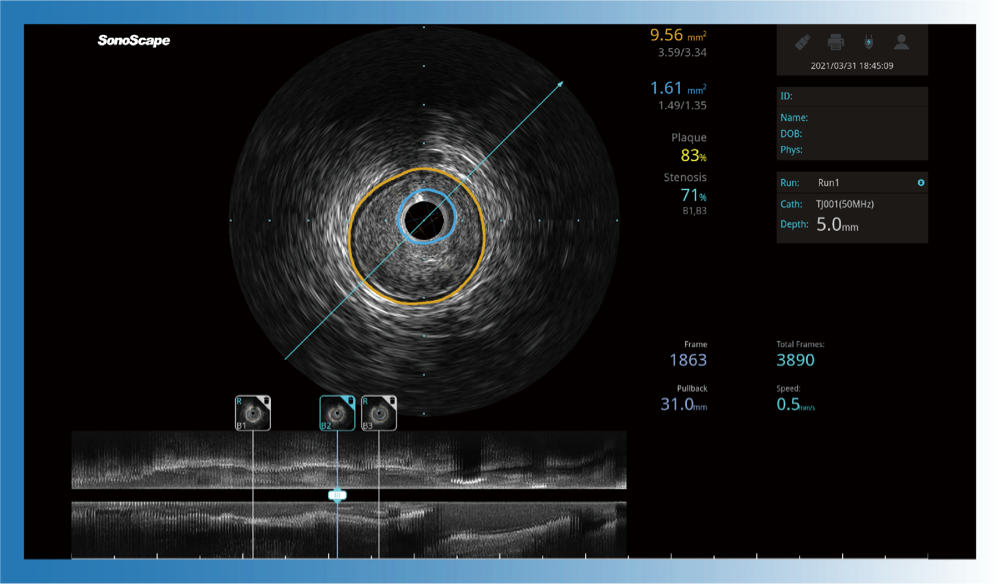

对比传统IVUS导管成像,1xBET宽频IVUS图像的近场支架梁显影更细腻,远场中膜外血管仍清晰可辨,兼顾远中近,兼顾分辨力与穿透深度

一键智能描迹,自动测量斑块负荷、面积狭窄率等指标,准确率高于90%